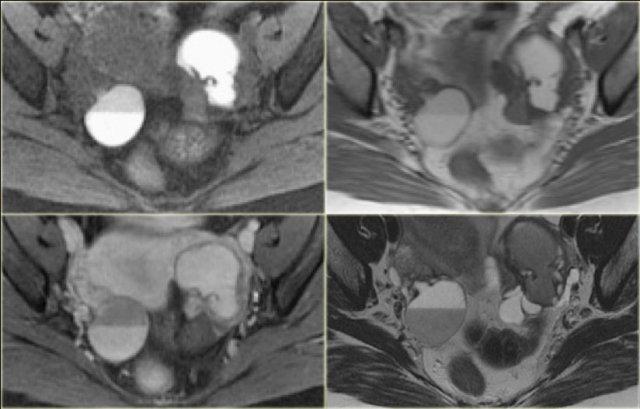

Hình ảnh chuỗi xung T2W mặt cắt ngang và mặt cắt đứng dọc của cùng một bệnh nhân.

Buồng trứng phải chứa nhiều nang đơn giản tăng tín hiệu T2 với bờ mỏng và không có thành phần đặc.

Trên hình mặt cắt ngang, có một tổn thương giảm tín hiệu T2, tức là nang phức tạp (mũi tên).

Có một lượng nhỏ dịch cổ trướng quanh buồng trứng phải, nhưng không đủ để gợi ý lo ngại về khả năng u tân sinh.

Trên chuỗi xung T1W không có kỹ thuật xóa mỡ, nang phức tạp tăng tín hiệu, gợi ý thành phần mỡ hoặc máu.

Trên chuỗi xung T1W có kỹ thuật xóa mỡ, tổn thương vẫn tăng tín hiệu, loại trừ tổn thương chứa mỡ.

Sau khi tiêm Gd, không có ngấm thuốc, xác nhận đây là nang buồng trứng xuất huyết.

Lạc nội mạc tử cung dạng nang (endometrioma) cần được đưa vào chẩn đoán phân biệt.

Lưu ý rằng hình ảnh trừ (subtraction) là tốt nhất để chứng minh sự vắng mặt của ngấm thuốc trong tổn thương tăng tín hiệu trên chuỗi xung T1W trước tiêm thuốc tương phản từ.